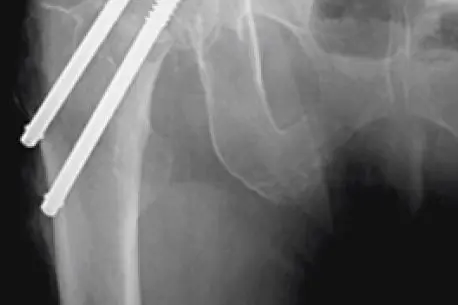

I nokre tilfelle kan brotet skruast saman ved hjelp av to skruar som blir sett inn i lårhalsen gjennom to små opningar i huda.

Lårhalsbrot behandla med to skruar.